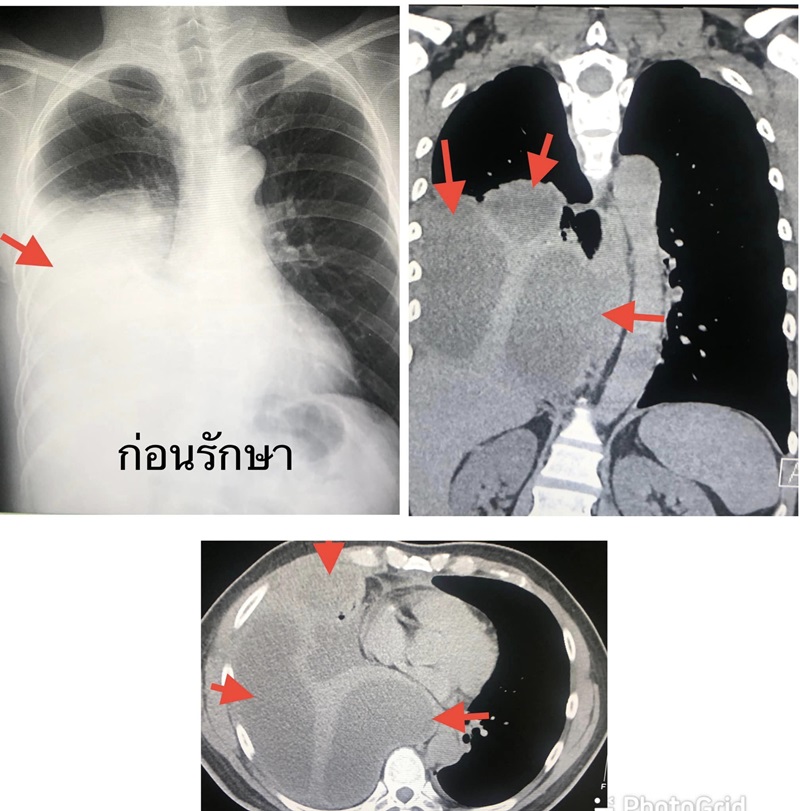

ตรวจร่างกาย มีไข้ต่ำ ๆ ฟังปอดข้างขวาได้ยินเสียงลดลง เจาะเลือด พบเม็ดเลือดขาวในเลือดสูง 16,030 เอกซเรย์ เห็นน้ำในปอดข้างขวา เมื่อทำคอมพิวเตอร์ปอดเห็นก้อนน้ำหลายก้อนเกาะอยู่ในช่องเยื่อหุ้มปอดข้างขวา

จากนั้นจึงรักษาด้วยการใส่สายระบายน้ำผ่านทางผิวหนังเข้าเยื่อหุ้มปอดข้างขวา 2 ตำแหน่ง ได้หนองสีเหลืองขุ่น มีกลิ่นเหม็น 1,200 ซี.ซี. ย้อมเชื้อพบแบคทีเรียทั้งกรัมบวกและกรัมลบ (gram negative bacilli, gram positive cocci in pairs and chains, gram positive bacilli) ให้ยาปฏิชีวนะทางเส้นเลือดครอบคลุมทั้งเชื้อแบคทีเรียที่ต้องการและไม่ต้องการออกซิเจน เพาะเชื้อแบคทีเรียขึ้น Streptococcus constellatus คงมีอีกหลายเชื้อ แต่เพาะไม่ขึ้น

ปรึกษาทันตแพทย์ เอกซเรย์พบฝีหนองที่รากฟัน (dental root abscess) ต้องถอนฟันทั้งหมด 9 ซี่ ทั้ง ๆ ที่ก่อนหน้านี้ ผู้ป่วยไม่รู้สึกปวดฟันใด ๆ หลังให้ยาปฏิชีวนะทางเส้นเลือด 1 สัปดาห์ อาการดีขึ้น เอกซเรย์ปอดดีขึ้น สุดท้ายนี้ จึงยกเคสดังกล่าวเพื่อเตือนให้ทุกคนต้องดูแลสุขภาพช่องปากและฟันให้ดี และอย่าปล่อยให้ฟันผุ